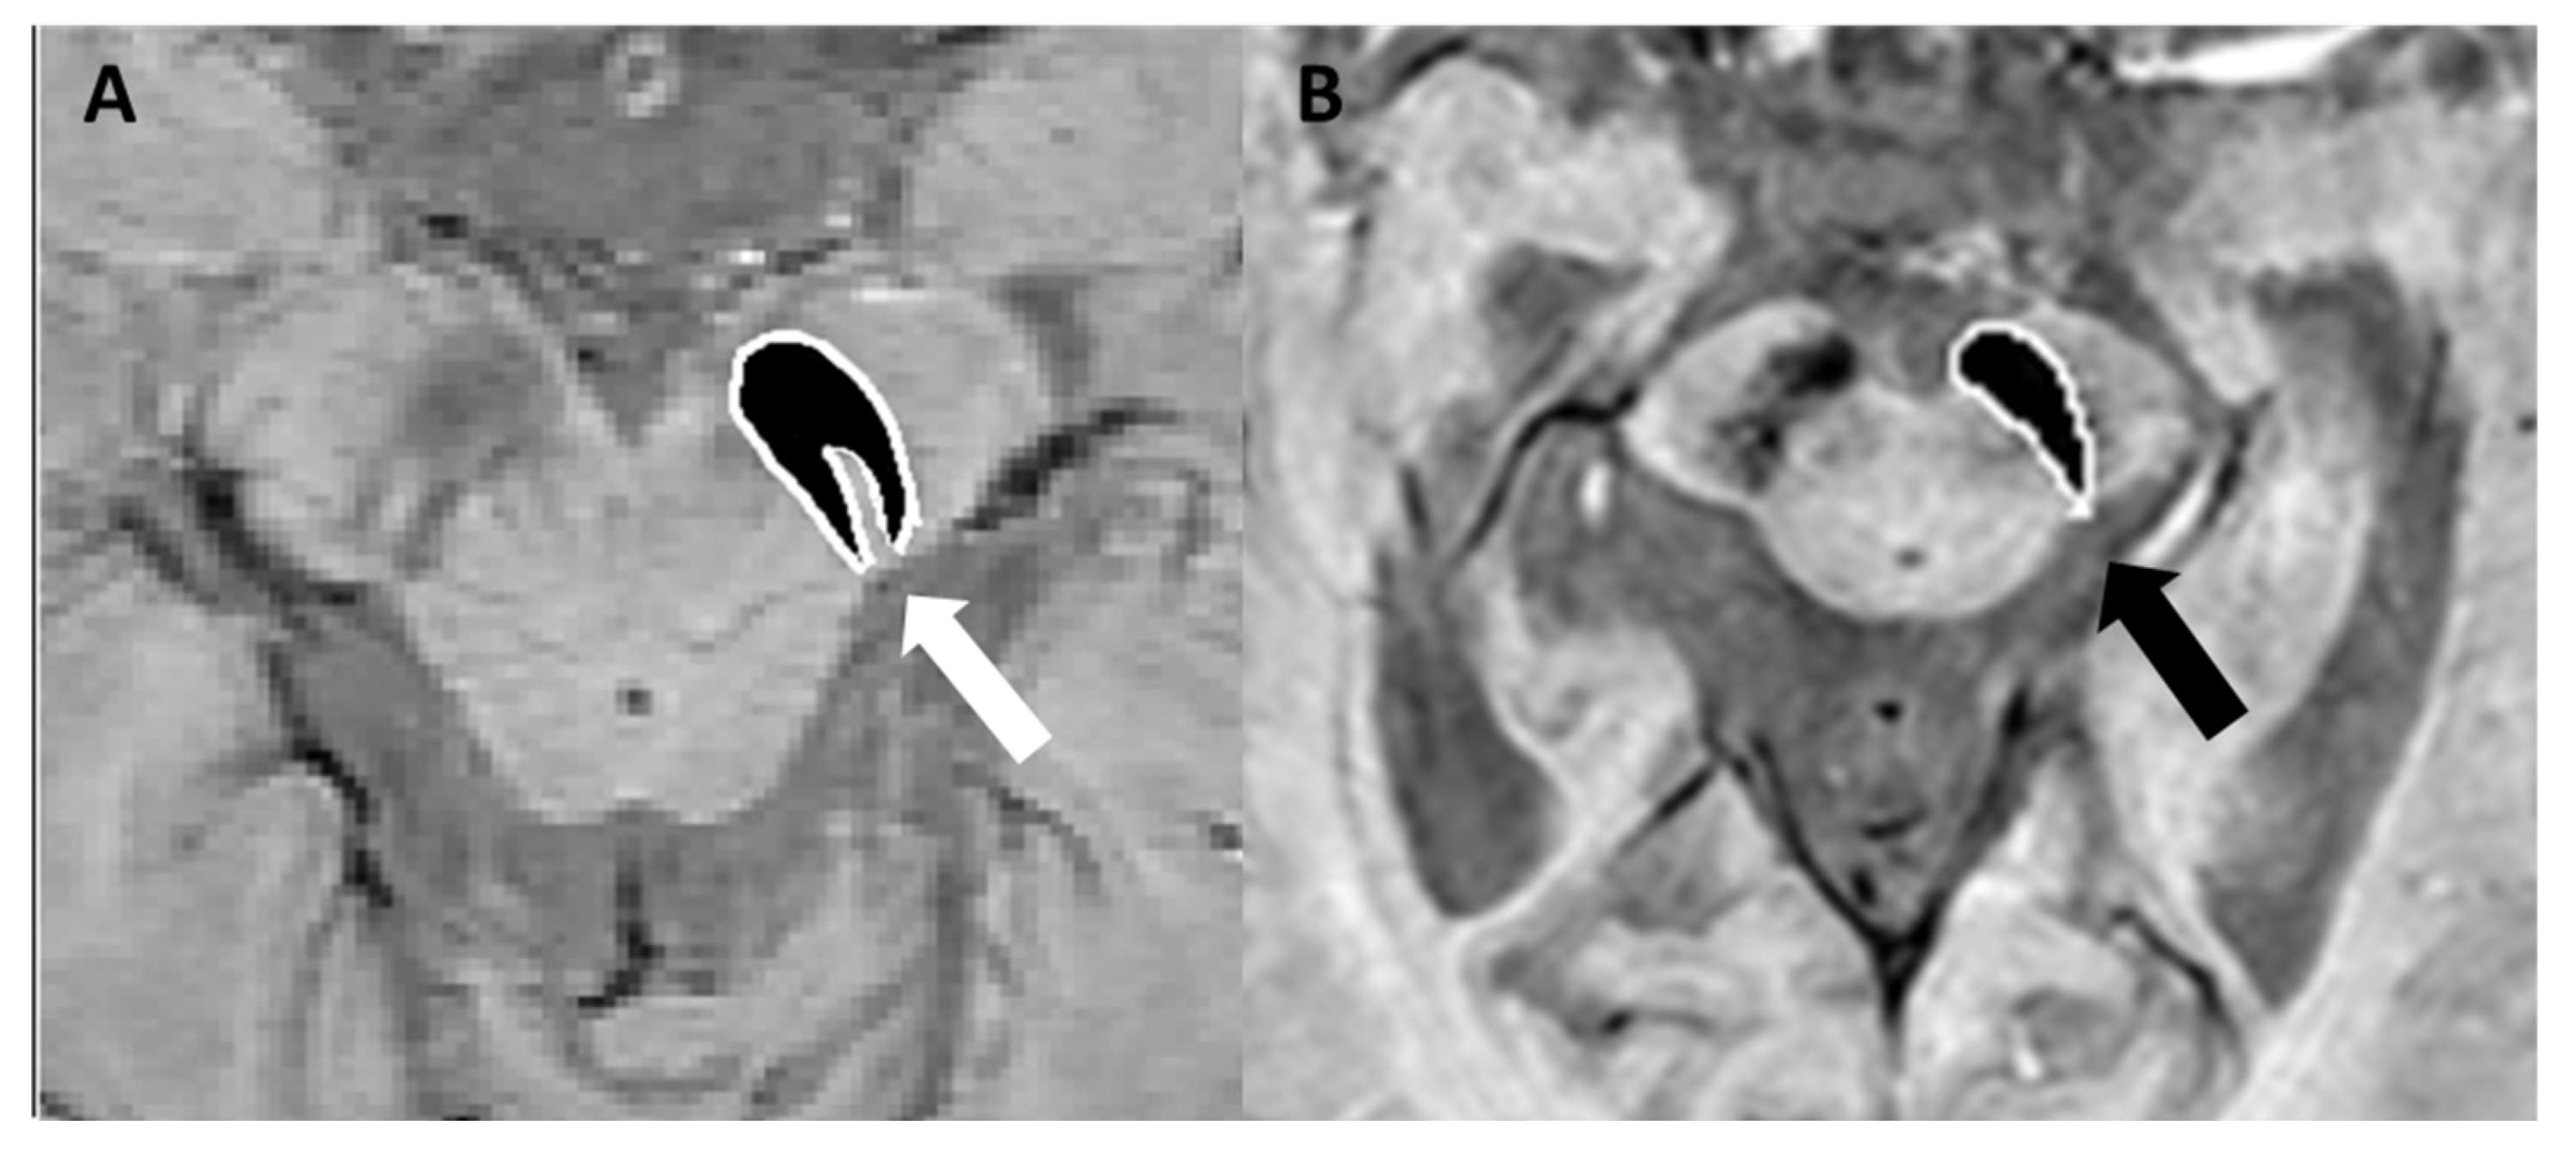

- Schwarz, S.T.; Afzal, M.; Morgan, P.S.; Bajaj, N.; Gowland, P.A.; Auer, D.P. The ‘Swallow Tail’ Appearance of the Healthy Nigrosome—A New Accurate Test of Parkinson’s Disease: A Case-Control and Retrospective Cross-Sectional MRI Study at 3T. PLoS ONE 2014, 9, e93814. [Google Scholar] [CrossRef] [PubMed]

- Cheng, Z.; He, N.; Huang, P.; Li, Y.; Tang, R.; Sethi, S.K.; Ghassaban, K.; Yerramsetty, K.K.; Palutla, V.K.; Chen, S.; et al. Imaging the Nigrosome 1 in the substantia nigra using susceptibility weighted imaging and quantitative susceptibility mapping: An application to Parkinson’s disease. NeuroImage Clin. 2020, 25, 102103. [Google Scholar] [CrossRef]

- Schmidt, M.A.; Engelhorn, T.; Marxreiter, F.; Winkler, J.; Lang, S.; Kloska, S.; Goelitz, P.; Doerfler, A. Ultra high-field SWI of the substantia nigra at 7T: Reliability and consistency of the swallow-tail sign. BMC Neurol. 2017, 17, 194. [Google Scholar] [CrossRef] [PubMed]

- Gao, P.; Zhou, P.-Y.; Li, G.; Zhang, G.-B.; Wang, P.-Q.; Liu, J.-Z.; Xu, F.; Yang, F.; Wu, X.-X. Visualization of nigrosomes-1 in 3T MR susceptibility weighted imaging and its absence in diagnosing Parkinson’s disease. Eur. Rev. Med. Pharmacol. Sci. 2015, 19, 4603–4609. [Google Scholar] [PubMed]

- Mahlknecht, P.; Krismer, F.; Poewe, W.; Seppi, K. Meta-analysis of dorsolateral nigral hyperintensity on magnetic resonance imaging as a marker for Parkinson’s disease. Mov. Disord. 2017, 32, 619–623. [Google Scholar] [CrossRef]